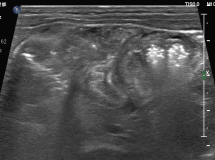

图3:肝区探查,见大量点状高回声相互簇拥着通过门静脉主干,涌入肝内;与此同时,可见肝左叶已散落分布着点、线状高回声,声影不明显。此外,肝周可探及少量不规则液性区。

图4:局部放大,可见大量点状高回声如车流般快速的通过门静脉“主干道”。

这不断涌现的点状高回声,究竟是什么?